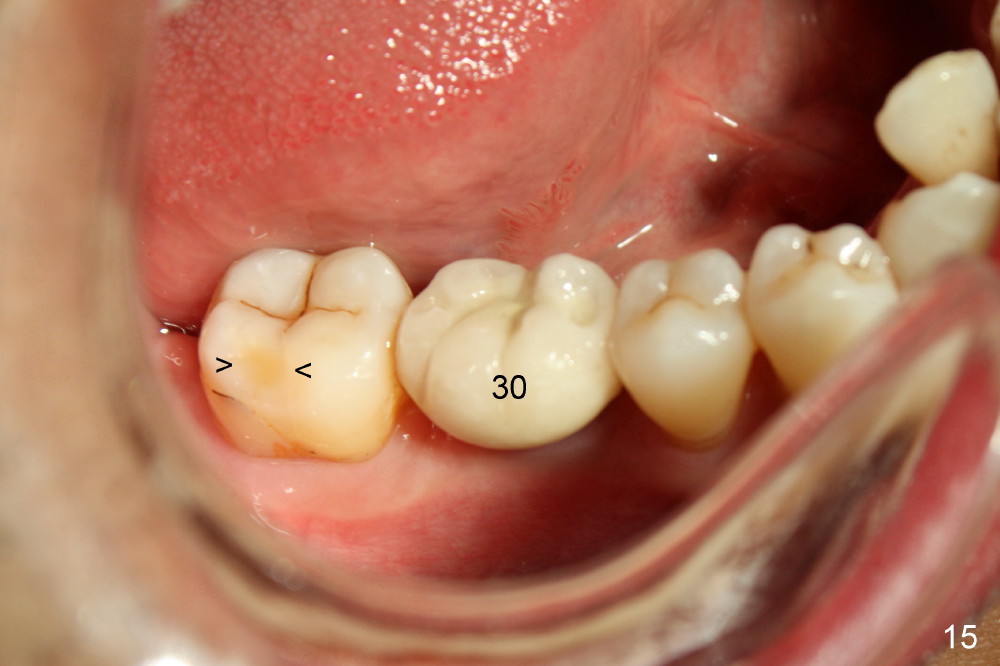

Fig.12-16 are taken 9 months after the orthodontic treatment. The lamina dura appears to form mesial and distal to the implant at the site of #30 (white arrowheads). There is no gross bone resorption associated with orthodontically moved teeth (Fig.12,13: #2,3,31). The posterior overjet remains normal (Fig.14). The arrowheads in Fig.15 indicate a worn facet, which was caused by the previous abnormal overjet (Fig.2). The alignment of the upper right quadrant also remains normal. The patient wears suction down retainers. He is pleased with improvement of mastication.